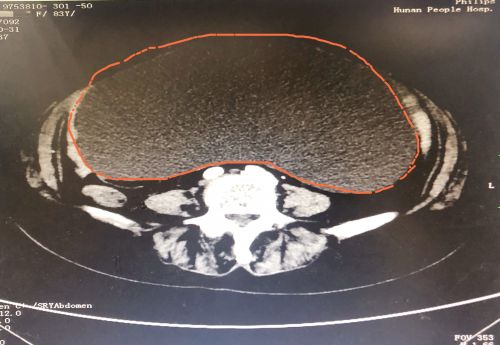

ct显示,肿瘤几乎占据老人整个盆腔和腹腔。

2021年1029日,彭娭毑住进湖南省人民医院妇科病房。完善相关检查发现,巨大的肿瘤几乎占据她整个盆腔和腹腔,并且压迫肠道和膀胱,这也是老人尿频的原因。与此同时,术前血液检查发现了异常——全系细胞减少,进一步骨髓穿刺结果为:可疑B细胞淋巴瘤骨髓浸润。